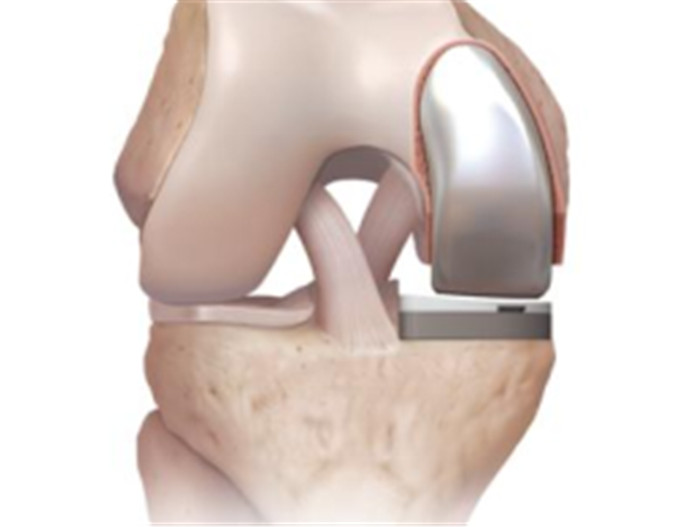

對于全膝關(guān)節(jié)置換術(shù)而言,膝關(guān)節(jié)單髁置換術(shù)是相對微創(chuàng)手術(shù),精準置換病損部位,用以替代膝關(guān)節(jié)股、脛關(guān)節(jié)損壞的軟骨表面和半月板,被稱為膝關(guān)節(jié)置換中的“補牙技術(shù)”,不需要去除前后交叉韌帶,最大限度保留病人的本體感覺和關(guān)節(jié)功能,實現(xiàn)膝關(guān)節(jié)置換手術(shù)的生理性重建。膝關(guān)節(jié)單髁置換手術(shù)具有損傷小、術(shù)后恢復(fù)快、手術(shù)外表美觀和住院時間短等優(yōu)點,是治療膝關(guān)節(jié)骨關(guān)節(jié)炎的理想辦法。目前,單髁置換技術(shù)是關(guān)節(jié)外科發(fā)展方向之一,隨著手術(shù)器械的發(fā)展和認識水平的提高,單髁置換術(shù)在臨床將會擁有廣泛的應(yīng)用前景。

羅軍主任表示:膝關(guān)節(jié)單髁置換術(shù)(unicompartmental kneearthroplasty, UKA)是相對全膝關(guān)節(jié)置換術(shù)而言的一種新型微創(chuàng)手術(shù),切口僅為原來的一半,且能最大限度地保留患者正常的關(guān)節(jié)部分,對患者的損傷更小,術(shù)后療效更佳,是骨性關(guān)節(jié)炎患者的一大福音。我院關(guān)節(jié)外科與運動醫(yī)學(xué)科在羅軍帶領(lǐng)下,已完成了20余例膝關(guān)節(jié)內(nèi)側(cè)單髁置換術(shù),均取得了非常好的治療效果,但外側(cè)單髁置換,在臨床上還是相對較少見,這類病人即使做全膝置換也比較棘手。我院緊跟國內(nèi)外醫(yī)學(xué)技術(shù)發(fā)展前沿,致力于為島城人民骨關(guān)節(jié)健康保駕護航。